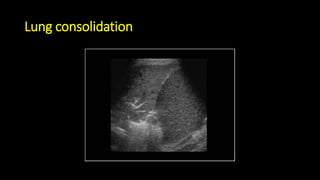

• Lung ultrasound to diagnose pneumonia with the

sensitivity of lung ultrasound was approximately 80 to

90 percent and the specificity approximately 70 to 90

percent. [4], [5]

Lung consolidation

DOI: 10.1186/2110-5820-4-1